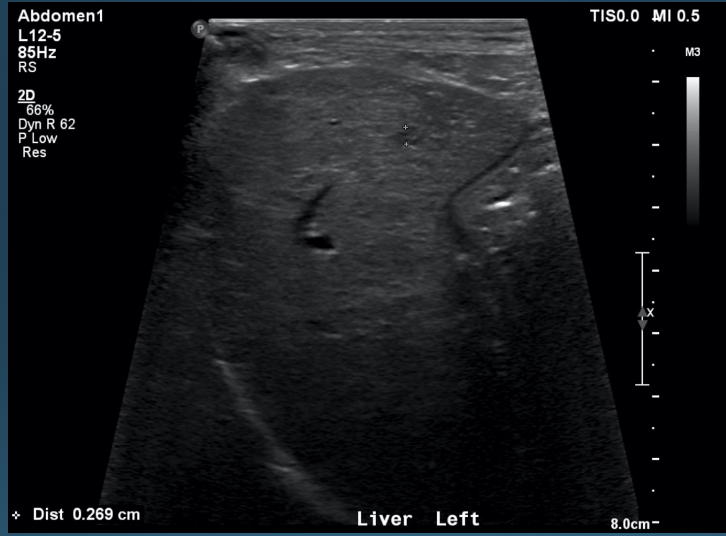

What is shown in these images?

normal ultrasound of the liver